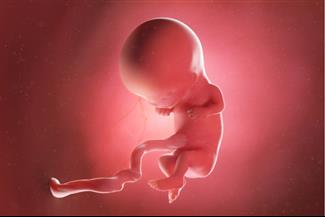

מאת: מערכת אינפומד 20/02/2019הוא אמנם עדיין קטנטן, אבל המוח, הלב, עמוד השדרה והשרירים של העובר שלך מתחילים להתפתח. ומה עובר עליך? לפניך כתבה על ... לכתבה המלאה

מאת: מערכת אינפומד 18/02/2019התינוק שלך הופך כבר לאיש קטן ומתחיל להצמיח סחוסים ותאי עצם. מהם השינויים המתרחשים בגופך ומדוע את צפויה לסבול מתנודו... לכתבה המלאה

מאת: מערכת אינפומד 18/02/2019בזמן שאת ממשיכה לסבול מעייפות וממצב רוח ירוד, חלק הארי של התפתחות האיברים החיוניים של העובר שלך עומד להסתיים. לפניך... לכתבה המלאה